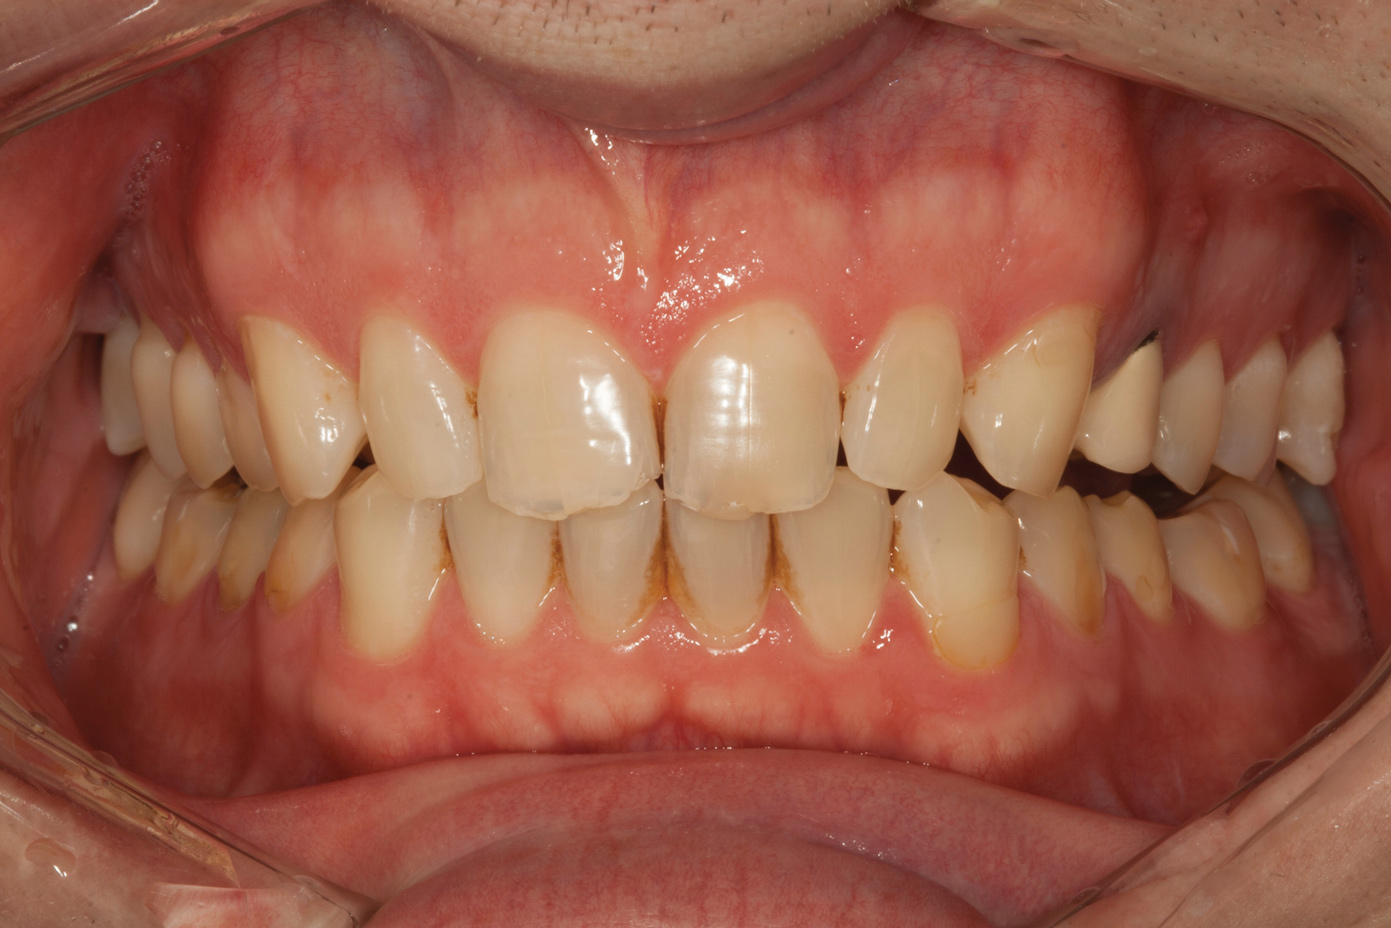

A 34-year-old male patient with no medical issues presented to the office with the chief complaint of a failing crown on tooth No. 12. The patient was also unhappy with his bite and the appearance of his teeth (Figure 1 and Figure 2).

A comprehensive examination was carried out, and preoperative photographs were taken (Figure 1 through Figure 4). The patient presented with fair oral hygiene and slight, generalized tissue inflammation. Caries and defective restorations were detected on teeth Nos. 4, 5, 13, and 14. The crown on tooth No. 12 was showing signs of leakage, and although the endodontic access cavity had been temporarily restored with composite, this endodontic re-treatment was acceptable and the tooth was otherwise symptom-free. Erosion was present on most of the posterior teeth and the cuspids, and abrasion was noted on teeth Nos. 4, 5, 10, 11, 20, 21, 22, 28, and 29. An examination of the patient's muscles, joints, and bite revealed no joint sounds, a normal range of motion, and negative joint load and immobilization tests.

The dentofacial examination revealed a low smile line with no incisor display when the lips were in repose. The anterior teeth were chipped and worn, and their overall color was darkened. The buccal corridors were deficient, and the failing crown on tooth No. 12 was visible in a full smile.

Fig 1. Preoperative smile photograph.

Figure 1

Fig 2. Preoperative retracted view.

Figure 2